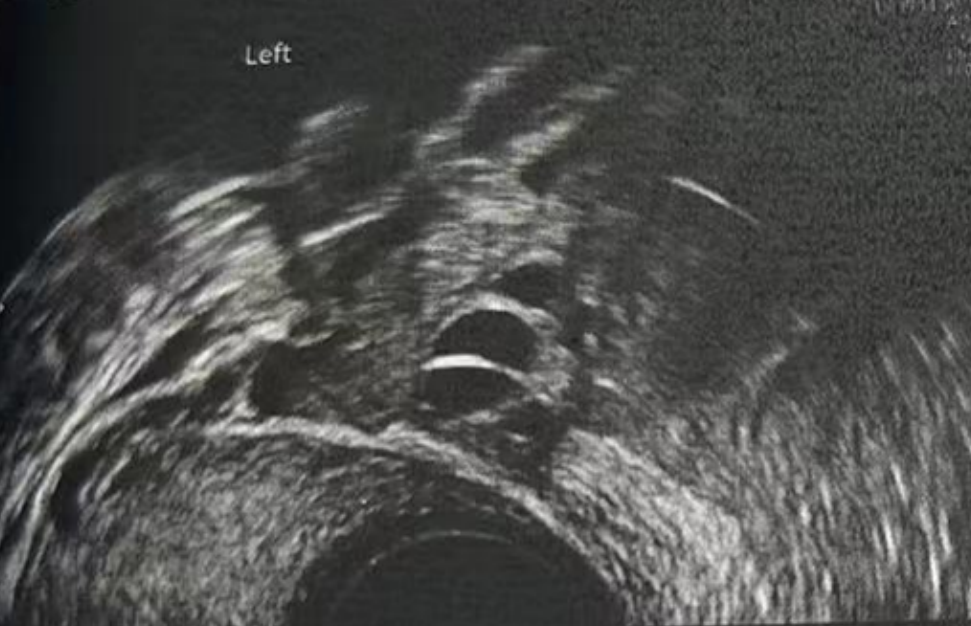

• 阴超检查:基础卵泡 6 颗

- 右侧卵泡 2 颗 (3-4mm)

- 左侧卵泡 4 颗 (3-5mm)

阴超检查:

- 右侧卵泡 2 颗

- 左侧卵泡 6 颗

- 右侧卵泡 2 颗 (10,20mm)

- 左侧卵泡 5 颗 (20,18,12,7,7mm)